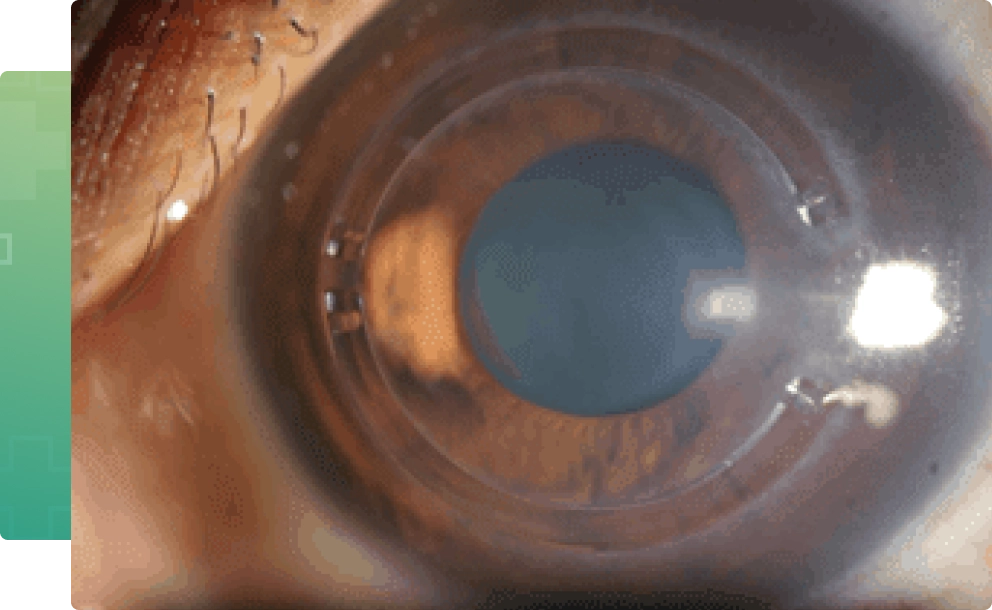

Slit-lamp examination

A vertical beam of light is used on the surface of your eye through a low-powered microscope to view your eye. He or she evaluates the shape of your cornea and looks for other potential problems in your eye like allergy etc which have a strong association with keratoconus.